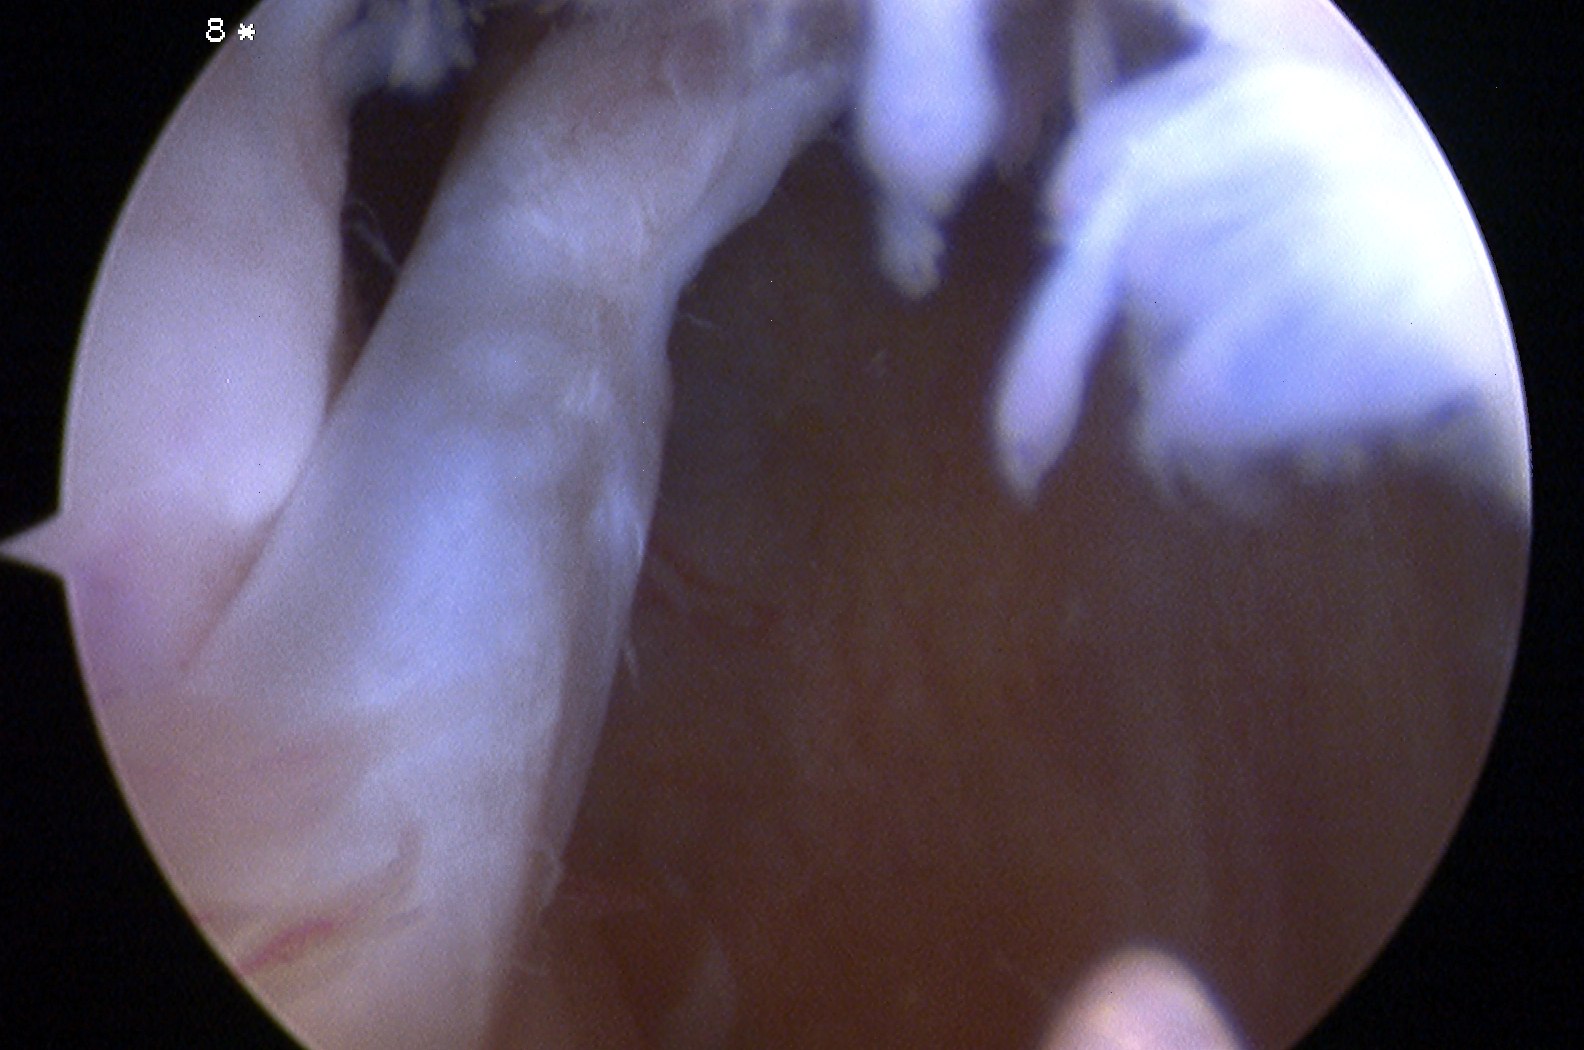

Cyclops lesion

Definition

- intercondylar notch fibrous proliferation

- a nodule anterior to and associated with the tibial graft insertion site

- anterior to tibial tunnel

- 5-10% of patients

Clinical

- painless, palpable and audible clunk upon terminal extension